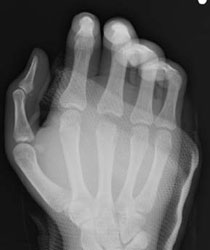

また単純レントゲン撮影は非常に有用であ る。関節内で骨に当たって折れたヒトの歯の破片が見つかることもある。化膿性関節炎・骨髄 炎の早期発見のためにも必須である。

11/18 のXp(図2)と比較し、11/25 のXp (図3-1,2)では第3中手骨骨頭が融解しており、 同日緊急で外科的洗浄施行。化膿性関節炎から 中手骨骨頭は腐骨と化しており、切除せざるを 得なかった。

術後は速やかに感染鎮静化したが、中指MP 関節の可動域制限を残し、治癒となった。(図4)

図2.11/18のXp

図3-1.11/25のXp

図3-2.11/25のXp

図4-1.術後Xp

図4-2.術後Xp